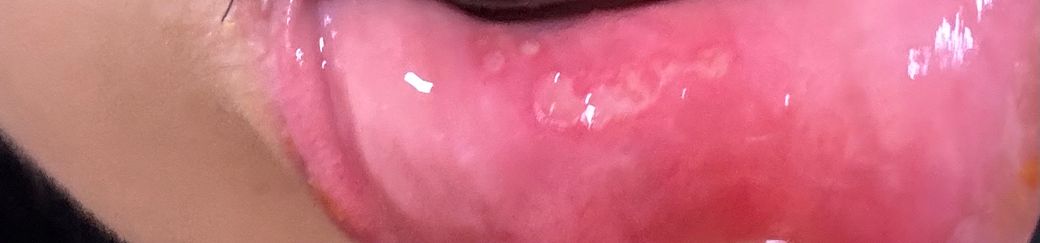

혹시 이렇게 생긴것도 구내염인가요?

며칠 전 잠깐 자다 일어났는데, 입술이 살짝 아리고 제가 잠결에 입술을 깨문거마냥 살짝 헐었더라구요.. 그러다 며칠 뒤부터 엄청 아프더니 이렇게 되었는데, 이것도 구내염 맞는거죠..? 이런 형태는 첨 보는거 같아서요.. ㅠㅠ

사진으로 봤을 때에는 구내염이 맞습니다. 일주일 이내에 소실 될 것이며 충분히 쉬시는 게 좋습니다.

구내염인거 같습니다. 최대한 자극이 가지 않도록 해주시는게 좋을것같습니다. 그리고 치과에 가셔서 소독도 한번받아보세요.

구내염일 가능성이 높아 보입니다. 구내염은 몸의 면역력이 떨어진 상태에서 점막조직에 상처가 생기고 감염이 되면 생기게 됩니다.

결과적으로 몸의 면역력을 높이기 위해 충분한 휴식을 취하는것이 좋습니다.

사진상 구내염이 생긴 것으로 보이며, 구내염은 1-2주 내에 저절로 없어지는 경우가 대부분입니다. 해당부위에 염증이 덧나지 않도록 소독용 헥사메딘 가글액으로 가글하여 관리하여주길 권합니다.